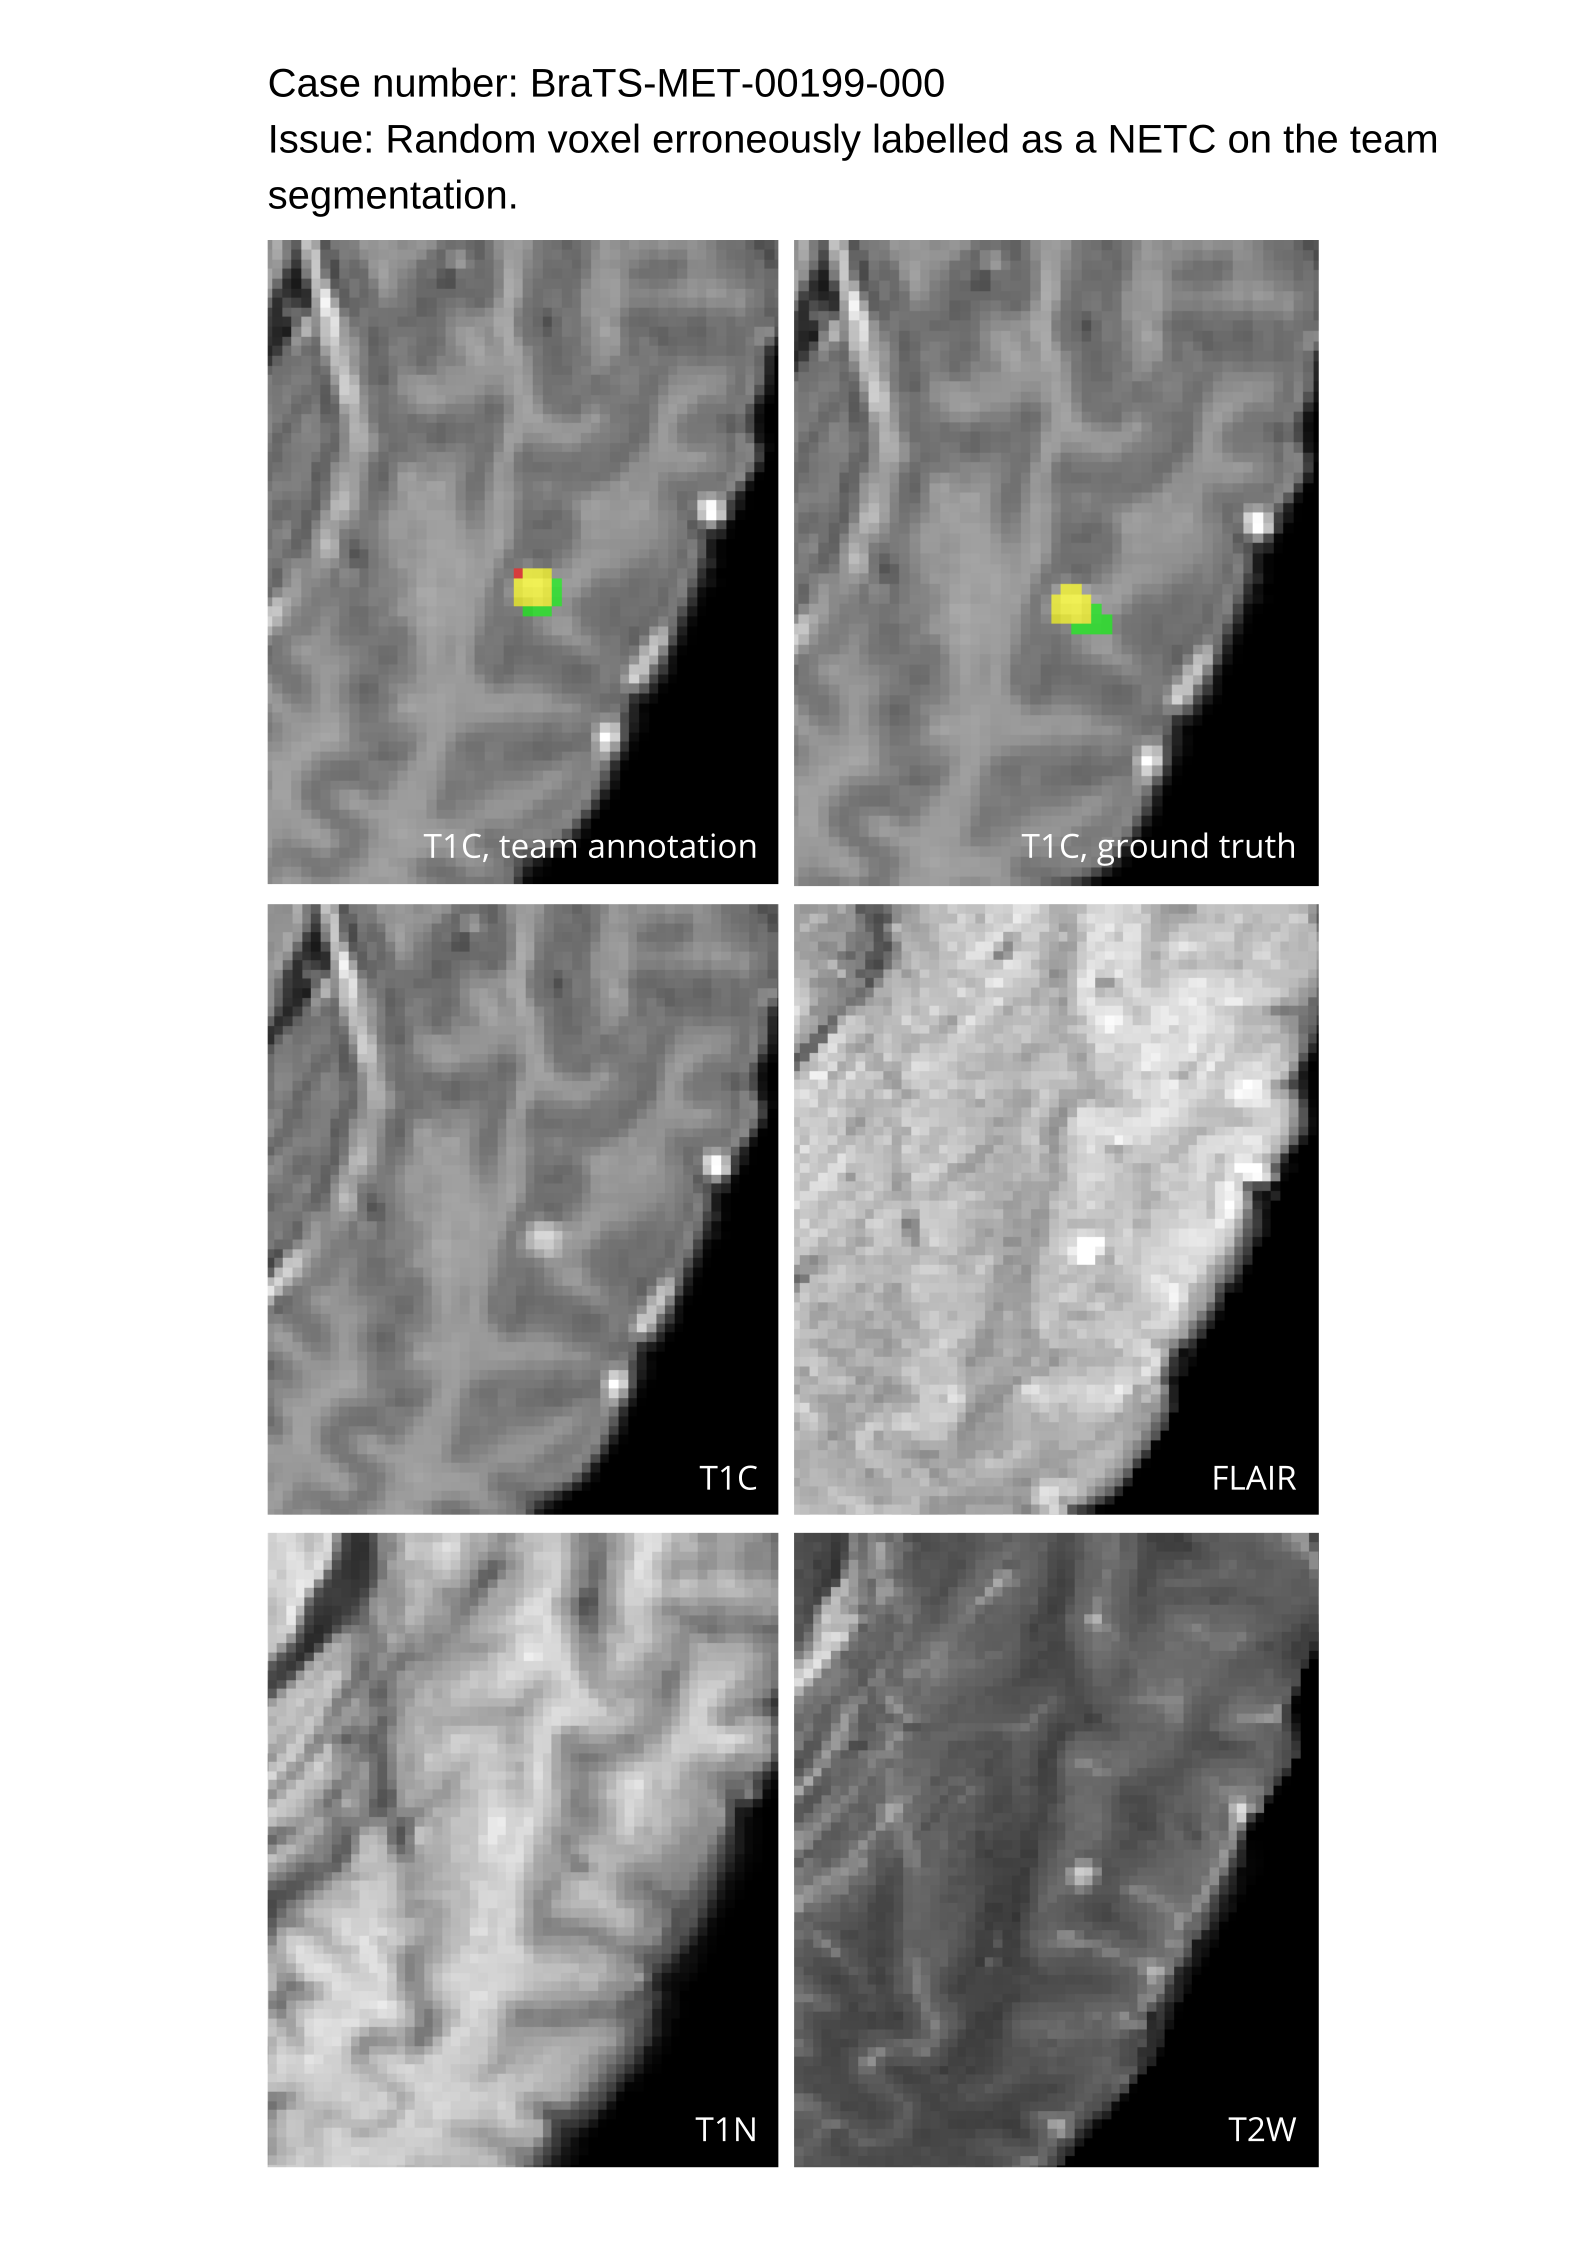

Approvers reviewed the volunteer annotations and either approved the case or returned it to students for re-annotation. Additionally, a QC process was implemented, which included removing all random voxels and any voxels outside the brain mask, ensuring all images had the same parameters (space, orientation, and origin) as the SRI24 atlas, and verifying the presence of all segmentations and segmentation masks are in the folder with original NIfTI images.

Acknowledging the variability in lesion significance arising due to human error, a volumetric threshold of 2 voxels (2 mm3superscriptmm3\text{mm}^{3}mm start_POSTSUPERSCRIPT 3 end_POSTSUPERSCRIPT) was established by an expert panel of clinical radiologists, below which the models’ performance on deemed ”small/false” lesions is not considered in the evaluation. This approach was primarily adopted to ensure that participants were not unfairly penalized for stray voxels in the GT labels, which may result from human error, or for small lesions unrelated to the pathology central to the challenge. The expert panel of clinical radiologists also determined the dilation factor, which was uniformly applied for combining lesions in the GT masks. A dilation factor of 1 voxel in 3D space was chosen because BMs can be small, and it is important to avoid combining these small BMs.

Table 4 provides the relative ranking for each team. Team NVAUTO ranked first in the challenge, with an average rank across subjects of 7.9 and a PatientWise mean of 0.38. Team SY placed second with a PatientWise mean of 0.41 across all patients. The supplementary material depicts the pitfall cases with figures illustrating the false positives or missed lesions.